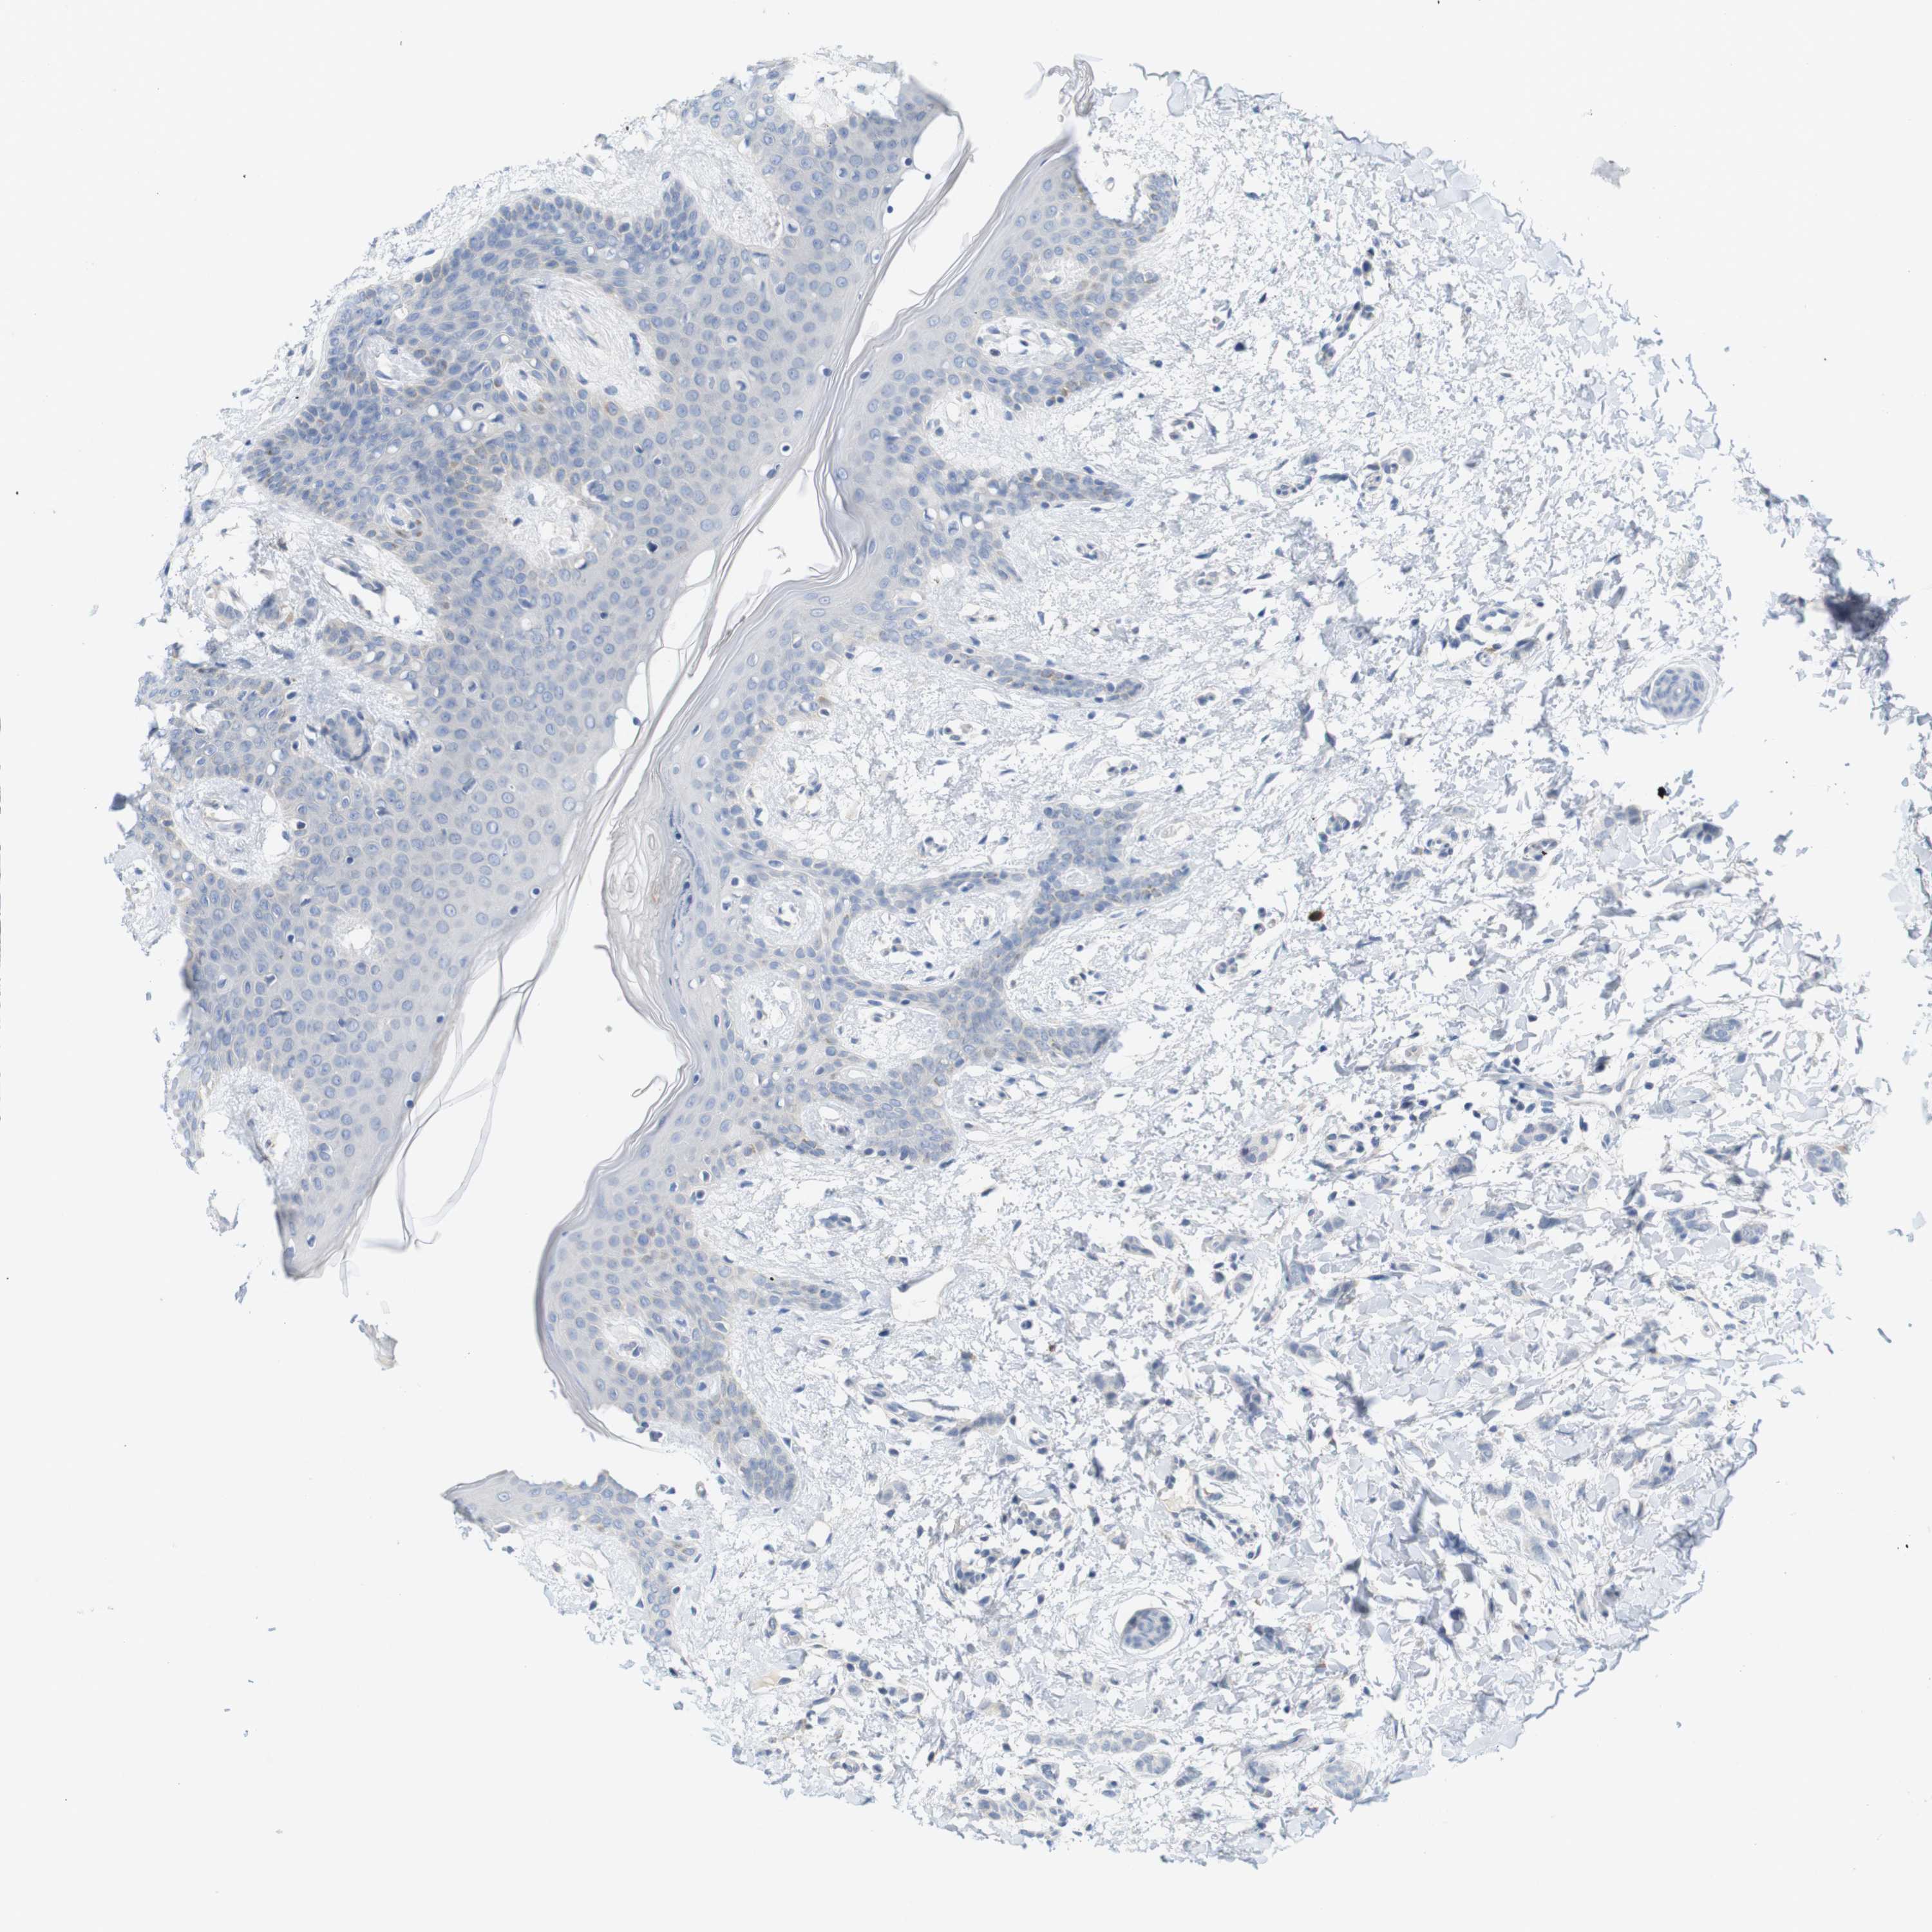

CANCER BREAST CANCER Show tissue menu

BRCA TCGA BRCA VALIDATION PROTEIN EXPRESSION

ANTIBODIES

AND

VALIDATION